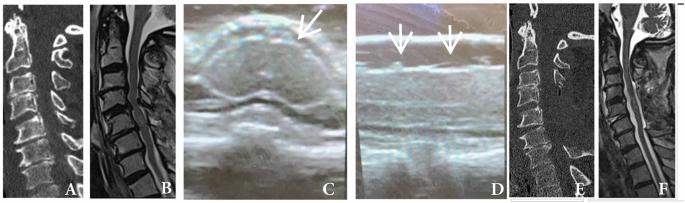

研究设计:调查。目的:术中超声(IOUS)是外科手术中评估脊髓损伤的一种新兴工具,特别是在创伤性脊髓损伤(SCI)后。这种技术的应用程度尚不清楚。为了评估在管理脊髓损伤患者中是否存在关于欠条的知识差距,对脊柱外科医生进行了一项国际调查。设置:国际调查。方法:使用由SCI专家委员会开发的基于网络的问卷调查AO Spine国际社区的成员。分类数据进行描述性分析。结果:在完成的276份调查中,22% (n = 61/276)表示在脊柱手术中使用了借据,大多数受访者来自欧洲(38% n = 24/61)和北美(30% n = 18/61)。只有41% (n = 25/61)接受过正式的欠条培训。59% (n = 36/61)的受访者表示,他们对急性脊髓损伤患者使用欠条,主要是为了评估是否足够的减压。在不使用借条的患者中,50% (n = 107/215)没有使用可用的超声机。总的来说,92% (n = 254/276)的人表示,白条培训课程将有助于提高理解和患者护理。结论:这项对脊柱外科医生的国际调查表明,目前在急性脊髓损伤的外科治疗中使用欠条的情况有限。了解脊柱外科医生的需求和调整教育机会可能会增加借据的作用。考虑到手术减压对提高急性脊髓损伤后预后的重要性,再加上借据评估减压的能力,更多地采用借据可以进一步提高减压手术的疗效。

Survey. Intraoperative ultrasound (IOUS) is an emerging tool for assessing the injured spinal cord during surgical intervention and particularly after traumatic spinal cord injury (SCI). The extent of utilization of this technique is unknown. To assess whether a knowledge gap exists regarding IOUS in managing SCI patients, an international survey of spine surgeons was performed. International Survey. Members of the AO Spine international community were surveyed using a web-based questionnaire developed by an SCI expert commission. The categorical data were analyzed descriptively. Of the 276 completed surveys, 22% (n = 61/276) indicated IOUS was utilized during spine surgery, with most responses coming from Europe (38% n = 24/61) and North America (30% n = 18/61). Only 41% (n = 25/61) had received formal IOUS training. There were 59% (n = 36/61) of respondents who indicated they use IOUS on patients with acute SCI, mainly to assess adequate decompression. Of those not using IOUS, 50% (n = 107/215) did not have access to an ultrasound machine available. Overall, 92% (n = 254/276) indicated that an IOUS training course would be beneficial to improve understanding and patient care. This international survey of spine surgeons demonstrated that currently, there is limited use of IOUS in the surgical management of acute SCI. Understanding the needs of spine surgeons and tailoring educational opportunities may increase the role of IOUS. Given the importance of surgical decompression in enhancing outcomes after acute SCI coupled with the ability of IOUS to assess decompression, greater adoption of IOUS could further enhance the efficacy of decompressive surgery.